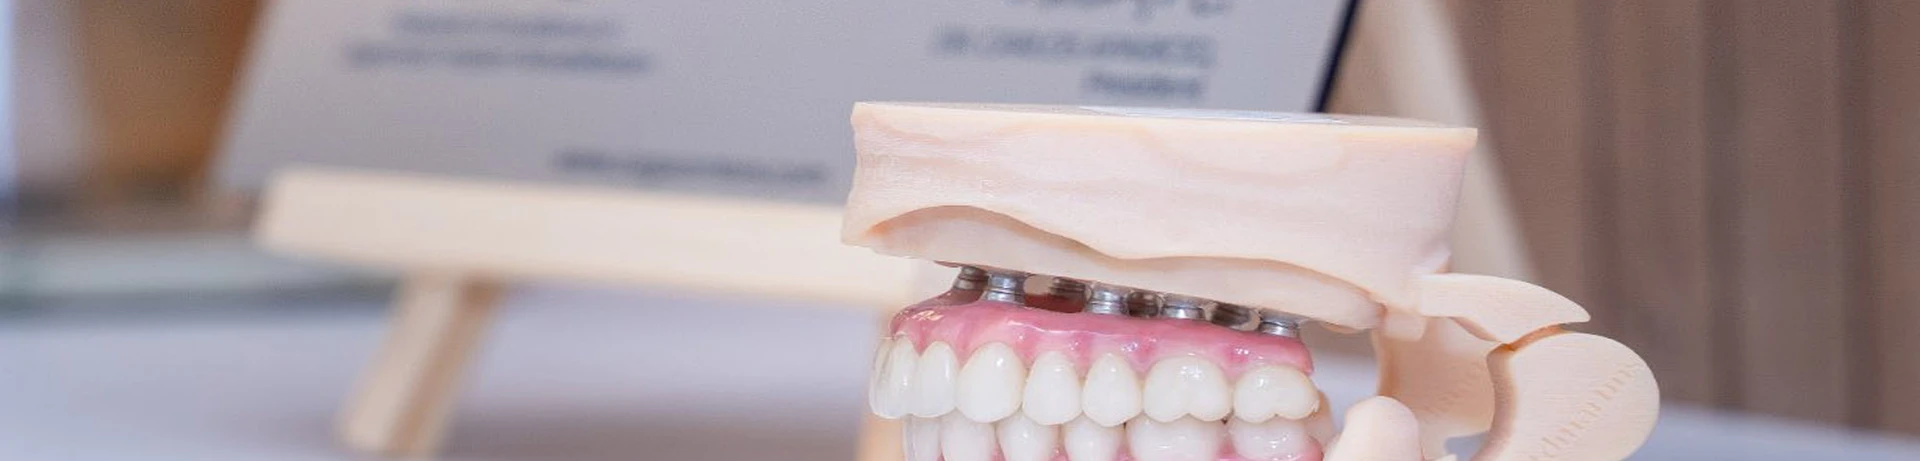

Tehnologia digitală de ultimă generație ne ajută să obținem cele mai precise și pasive lucrări dentare. Pacienții simt lucrările dentare fixate precum dinții naturali.

Sistemul Dantură pe implanturi dentare implică un număr redus, dar totuși extrem de eficient de implanturi dentare, care inserate în poziții cheie conferă siguranța de care ai nevoie / siguranța unei danturi sănătoase. Mai mult decât atât, această intervenție este minim invazivă, iar recuperarea este mult mai ușoară.